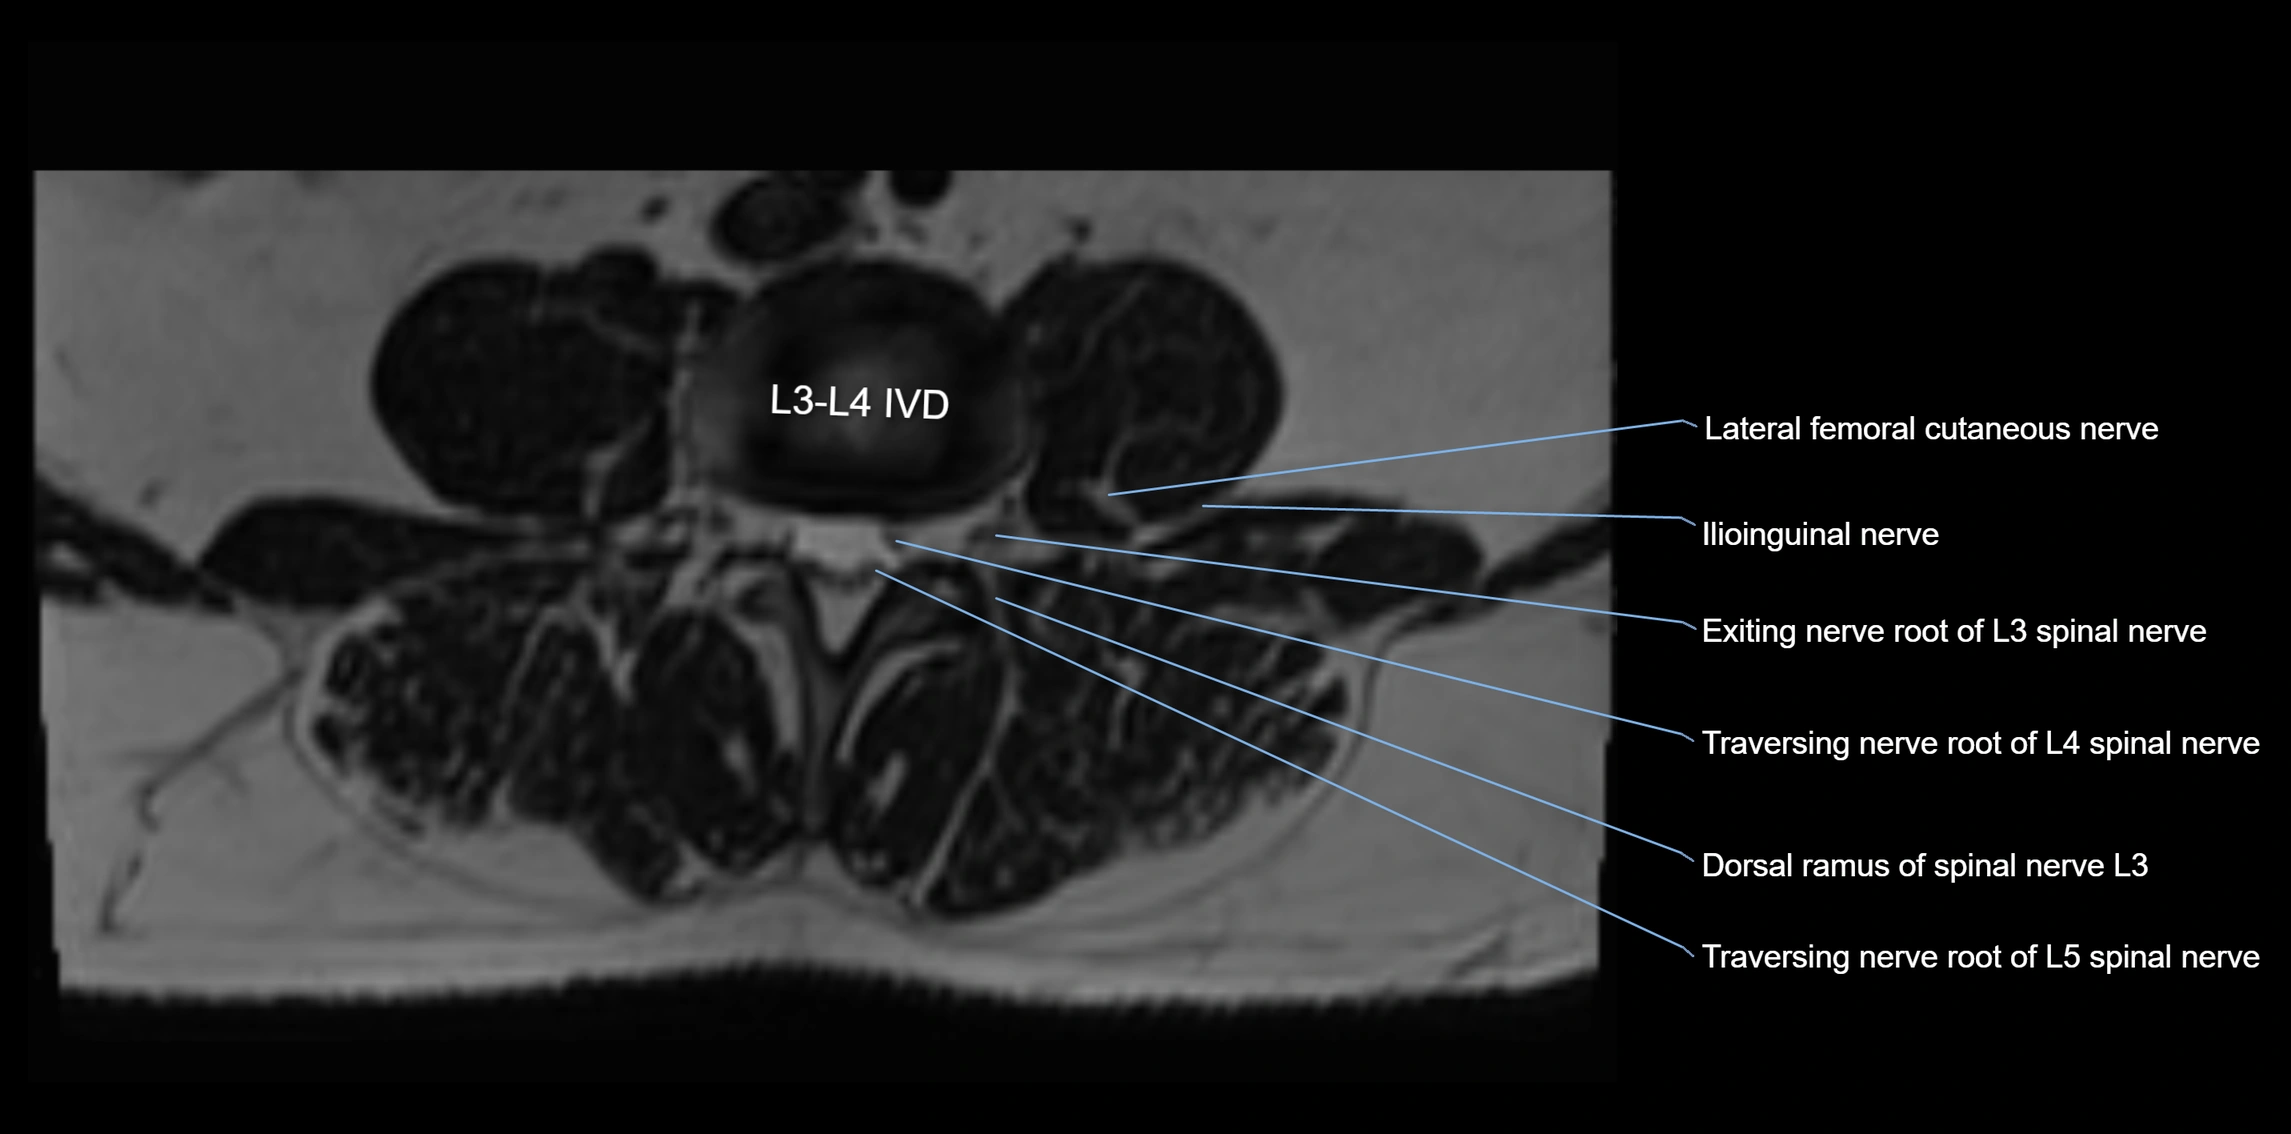

MRI Appearance

T1-weighted images:

• Nerve appears as a very thin low-to-intermediate signal intensity structure

• Surrounded by bright fat, aiding visualization

T2-weighted images:

• Nerve shows intermediate to mildly hyperintense signal compared to muscle

• Pathological involvement appears brighter

STIR (Short Tau Inversion Recovery):

• Normal nerve appears dark

• Inflamed or entrapped nerve appears bright hyperintense

T1 Fat-Sat Post-Contrast:

• Normal nerve enhances minimally

• Pathologic nerve (neuritis, entrapment, tumor infiltration) shows focal or diffuse enhancement

3D T2 SPACE / CISS:

• Nerve appears intermediate to mildly hyperintense compared to muscle

• Surrounded by bright fat or CSF, improving visualization

• Best sequence for mapping small pelvic nerves such as the anococcygeal